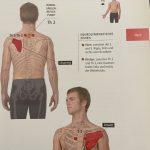

b/ Cơ liên quan:

– Cơ hoành (Diaphragma): Ảnh hưởng nhịp tim khi thở

– Cơ ức đòn chũm, liên sườn, cơ cổ trước: Căng thẳng có thể ảnh hưởng nhịp tim

(Hình ảnh đính kèm:)